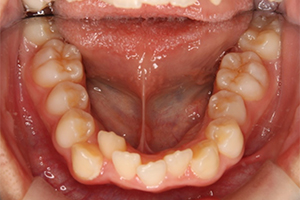

矯正治療のCASE 05

Before

After

-

- 主訴

- 歯並びがガタガタしていて清掃しにくい

- 治療内容

- ラビアル矯正(表側)

抜歯あり

- 治療費用

- 88万円~(税込)

- 治療期間

- 20か月

【リスク・副作用】

歯の痛み、口内炎、歯磨きがしにくいことによるむし歯や歯周病のリスク、歯根吸収や歯の変色、後戻りなどの副作用があります。